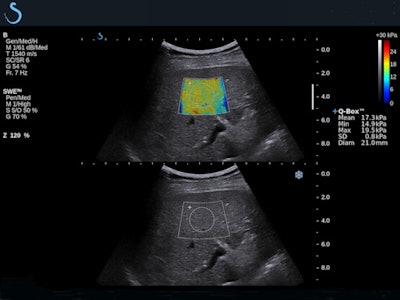

Over the past decade, several studies have demonstrated the benefits of SWE for assessing liver stiffness quantitatively, noninvasively, and accurately.7 SWE has been shown to yield accurate diagnostic measurement of liver fibrosis in a range of patients, from hepatitis C patients to cirrhosis, including those with ascites.8

One of the more recent studies found the moving images obtained this way accurately measured incidentally discovered liver lesions in patients with no history of liver disease; another found that SWE aided the detection of portal hypertension, a dangerous complication of cirrhosis.9 Two-dimensional images obtained noninvasively were especially important for monitoring the progression of liver disease in vulnerable patient populations such as those suffering from chronic viral hepatitis.